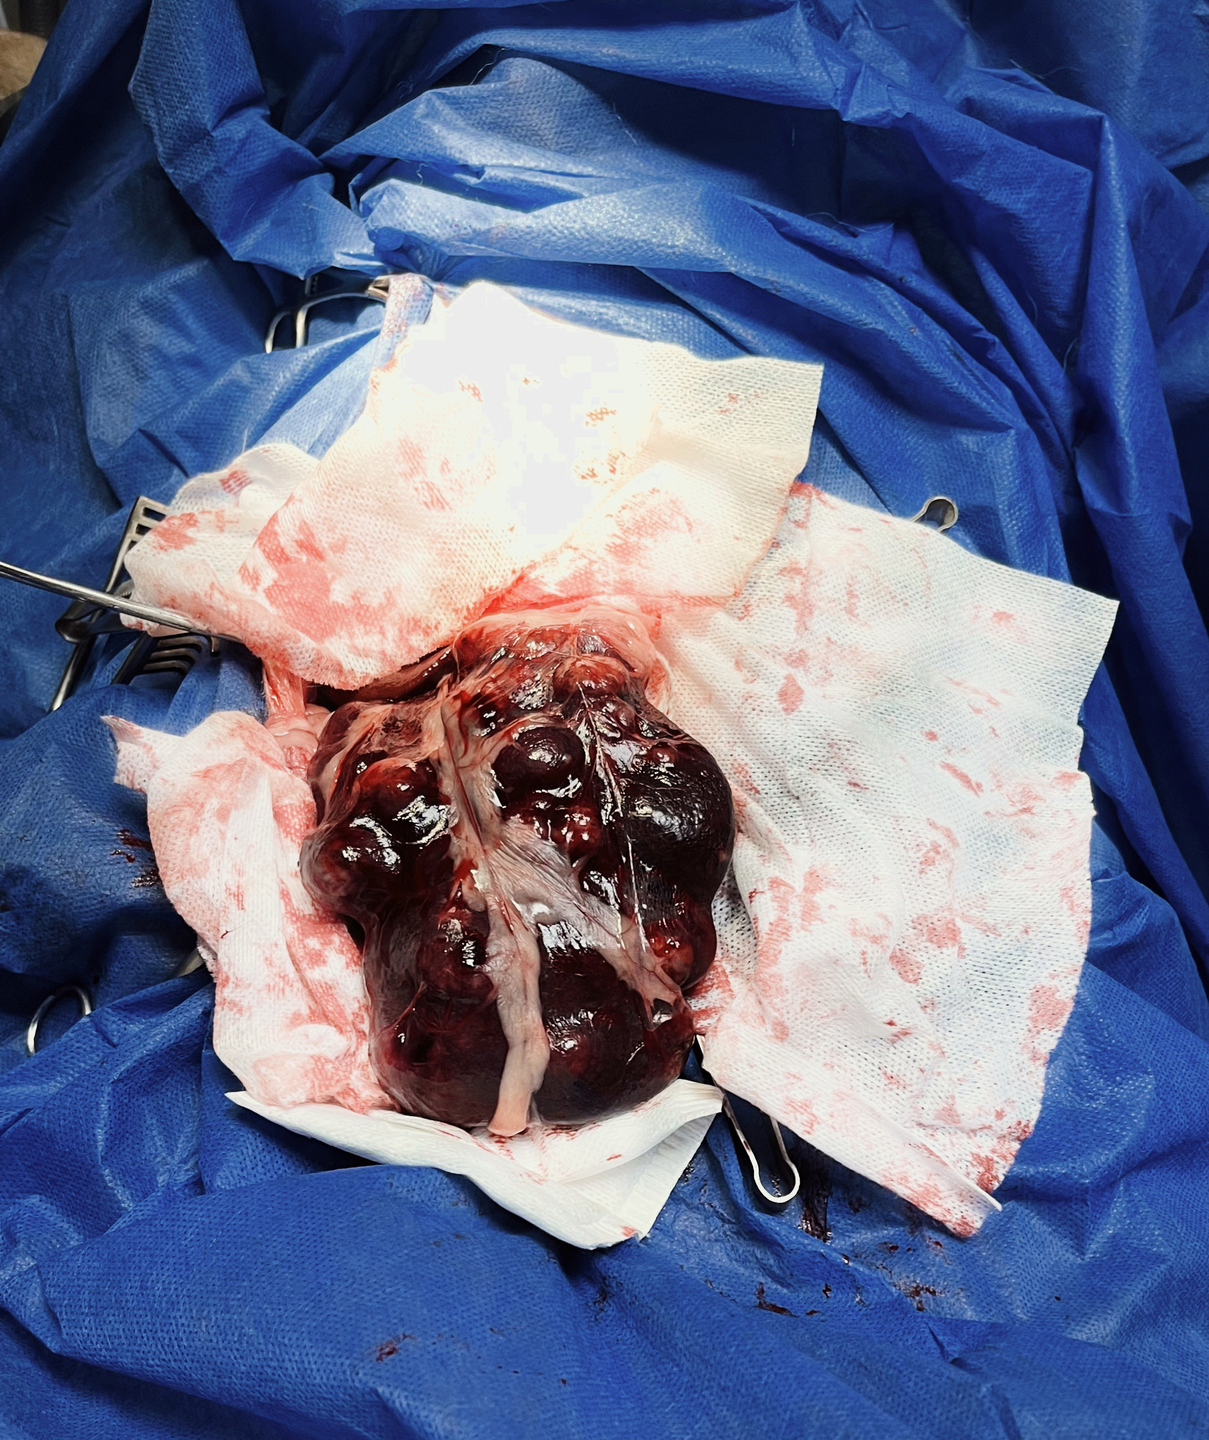

• Large, irregular splenic masses (~18 cm )

• Splenic mass

The standard of treatment for splenic hemangiosarcoma's that have not yet metastasized to the lungs consists of surgery to remove the measurable (bulky or visible) disease followed by chemotherapy to delay the progression of metastatic disease

histologically mass was confirmed Hemangiosarcoma